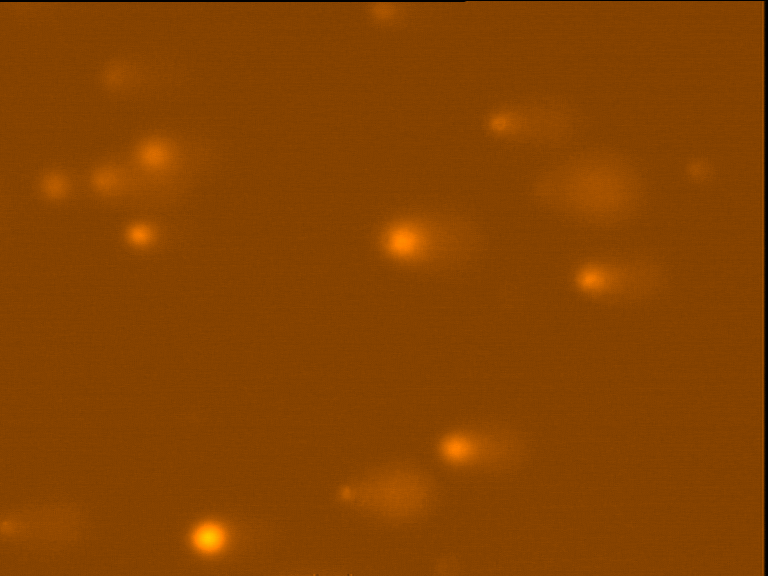

Forty eight hours after treatment, an alkaline SCGE assay was performed, and apoptotic cells were scored under a fluorescent microscope following staining with ethidium bromide. Morphological studies were done by counting the cells under the microscope after completing the cells’ 48-hour incubation period s with different sub-groups of P-gp reversal agents.

Following these criteria, a total of 600 randomly selected cells from each sample of Rajisubcell lines were observed for apoptosis using a fluorescent microscope. To confirm morphological assessments of apoptosis and necrosis, smears were stained with ethidium bromide. The cells were centrifuged, and pellets were re-suspended in minimum volumes of PBS.

Fig. 4 through 6 show the morphological features of Raji cell sub-lines exposed to DOX, indomethacin, or verapamil. Some of the reversal agents significantly increased the frequency of apoptotic cells compared with control cells. Thus, the P-gp reversal agents were able to overcome apoptotic resistance in the NHL cell-line model. Apoptotic cells in the controls contributed approximately 10% of the whole population (i. e., 61/600 x 100 = 10.16% for TK+ and 69/600 x 100 = 11.5% for TK-). After exposure to the P-gp reversal agents, apoptic cells increased to 22.3% with indomethacin and to 43% with doxorubicin in TK+ cells. In TK- cells, apoptic cells increased from 11.5% to 26.8% and 75.7% with indomethacin and doxorubicin, respectively.

Fig. 4: Comet images of the Raji cell sub-lines after treatment with 25 nM DOX for 48 hours in 37°C and 5% CO2. TK+ treated cells (left). And TK- treated cells (right), as photographed with the Leica microscope below X 200

Fig. 5: Morphological features of Raji TK+ cells after treatment with indomethacin (1), verapamil (2) and DOX (3). In each row, left images show intact cells, middle images show apoptotic cells, and right images show necrotic cells as they appeared under the microscope X 200